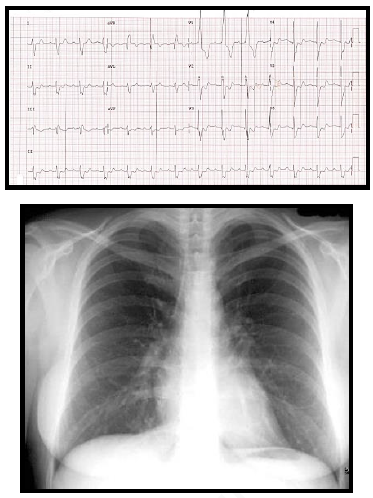

Paciente de 34 anos, G3P1A2, no décimo dia de

puerpério, deu entrada no pronto socorro com

queixa de dor torácica associada a dispneia

importante. Ao exame físico apresenta regular

estado geral, corada, hidratada, afebril,

ausculta pulmonar sem alterações, taquipneia

(frequência respiratória de 30 ipm) com

saturação de oxigênio de 84% em ar ambiente,

ausculta cardíaca sem alterações, frequência

cardíaca de 108 bpm e pressão arterial de 86 x

54 mmHg. O eletrocardiograma e o RX de tórax

estão demonstrados nas figuras abaixo. Os

exames laboratoriais demonstram Troponina =

0,9 mcg/dl (Valor normal < 0,01 mcg/dl) e

Peptídeo Natriurético Cerebral (NT pró-BNP) =

1314 pg/dl (Valor normal < 200 pg/dl).